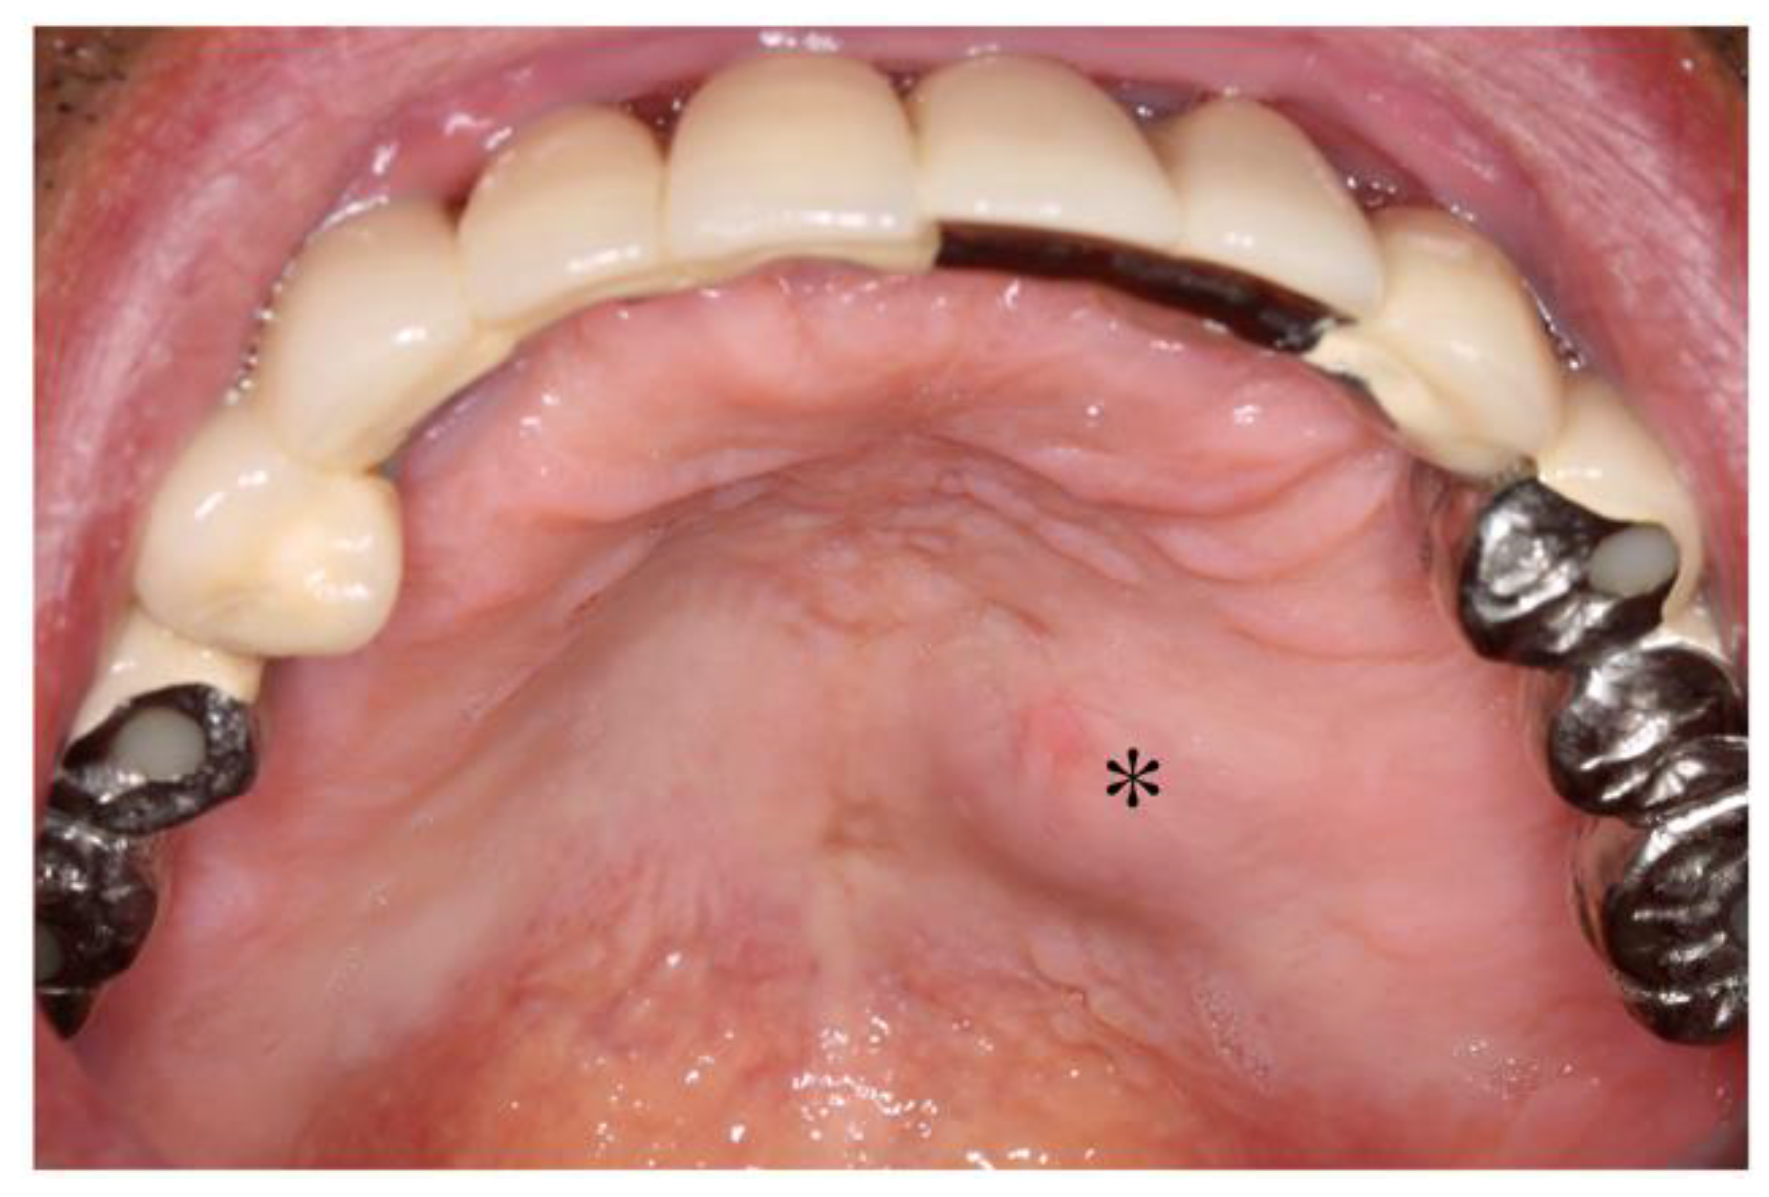

2.2. Dental Examination

2.3. Referral to an Otolaryngological Specialist

2.4. Follow-Up